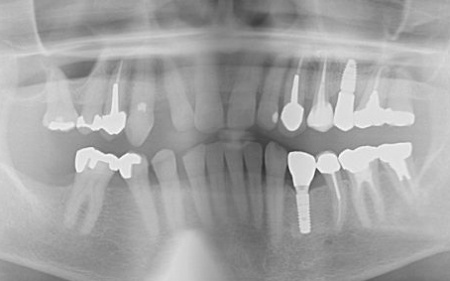

70代女性 歯根が割れた左下奥歯を抜きインプラントで噛み合わせを回復させた症例

レントゲン撮影を行って詳しく拝見したところ、左下奥歯(第1小臼歯)の歯根が割れていました。

まず、周辺組織に負担をかけないよう配慮しながら、慎重に左下奥歯(第1小臼歯)を抜きます。

抜歯後は骨や歯茎の回復を待ち、口腔内の状態が安定したことを確認して、インプラント埋入手術へ進みました。